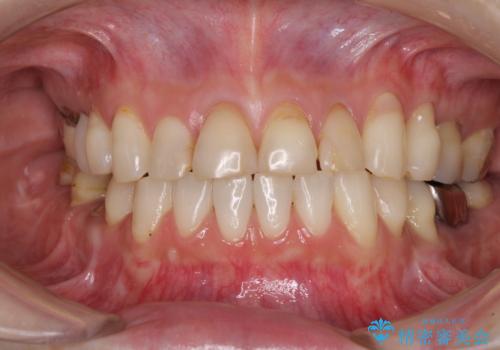

- 前歯の虫歯や治療跡が気になるとのことで来院された患者様です。

以前矯正治療をされ、その時には歯列が整ったので満足されたそうですが、若干の後戻りにより隙間ができ、矯正治療前に治療していた虫歯の跡が気になったため、オールセラミックによる審美治療を希望されました。

目立つ範囲である前歯4歯をオールセラミッククラウンにて補綴することとしました。